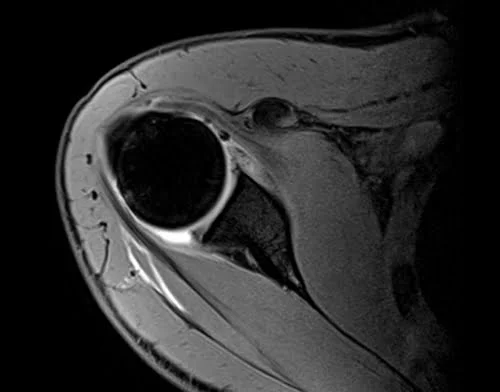

VIBE FAT SAT AXIAL POST JOINT INJECTION SEQUENCE USED IN SHOULDER ARTHROGRAPHY IMAGING